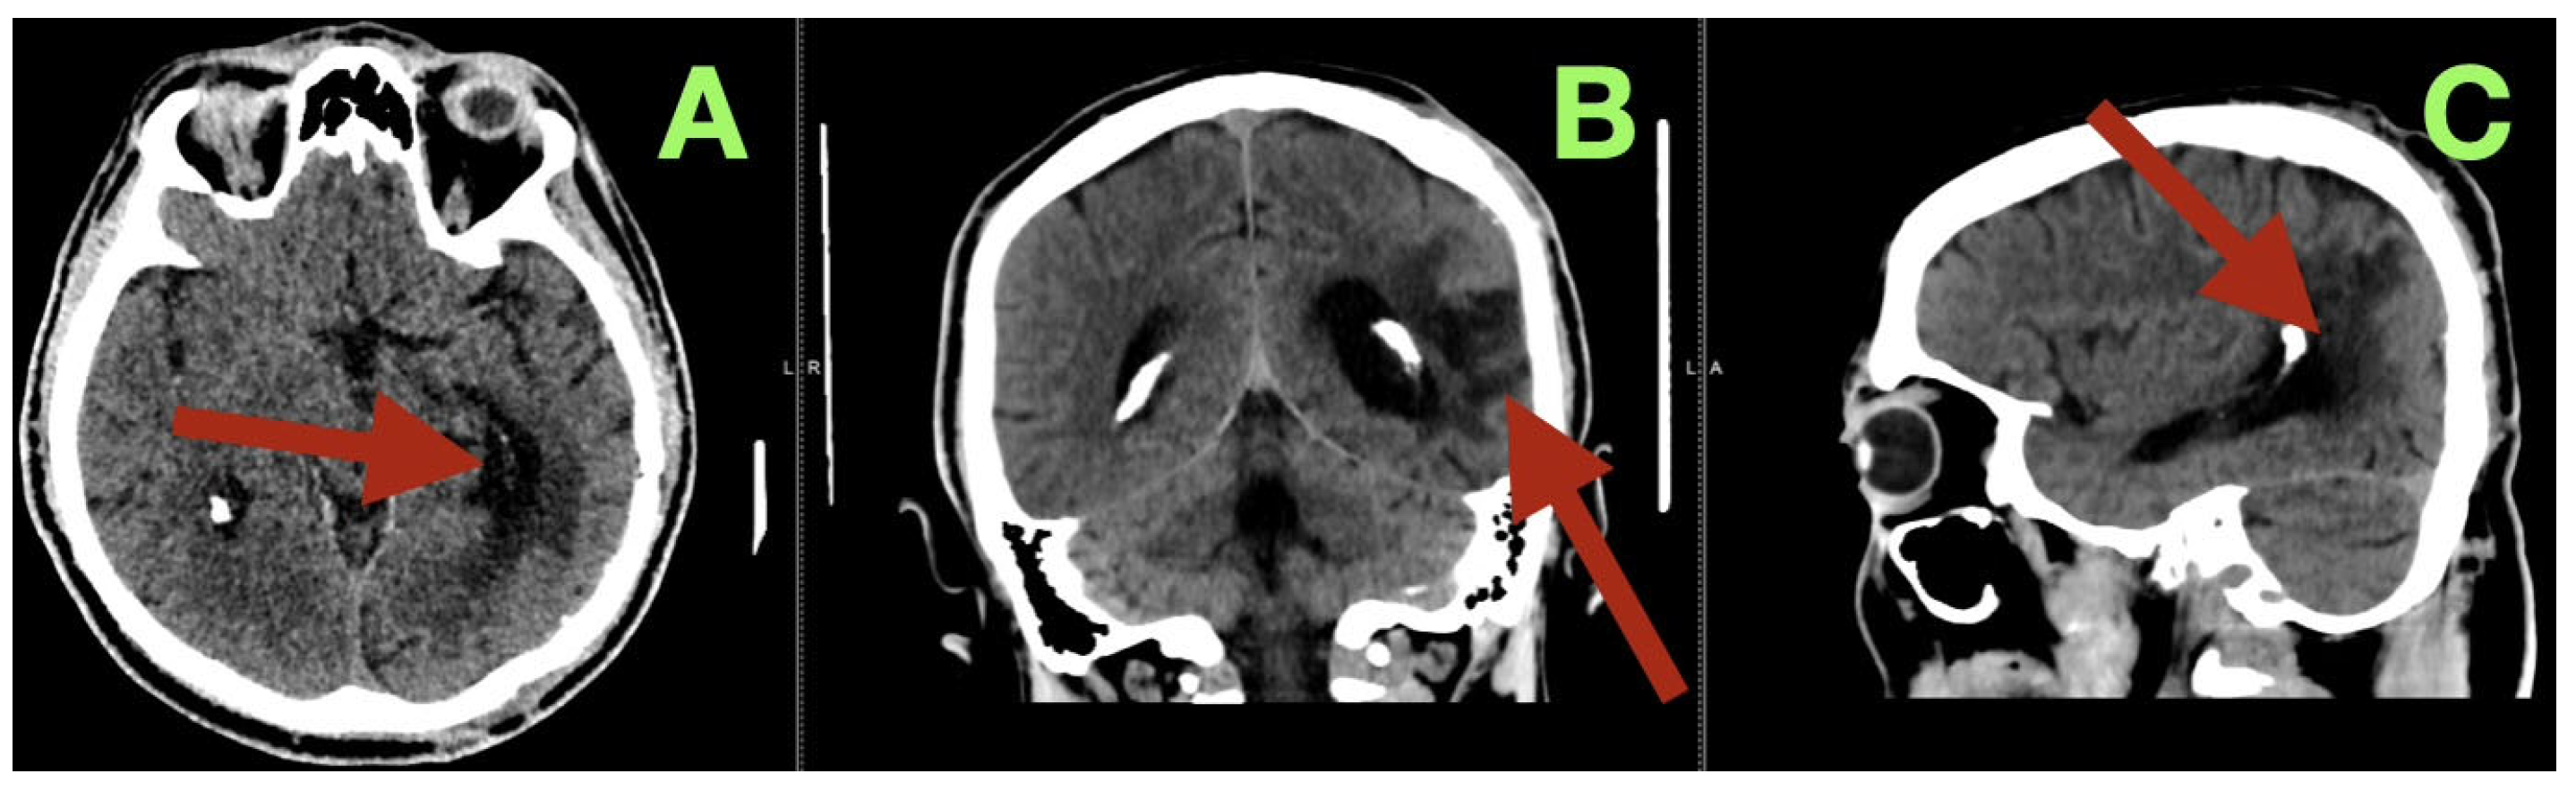

By the third postoperative day, the patient began to read and write spontaneously, and was participating in cognitive exercises with the speech therapy team. The patient demonstrated some subtle improvement in the speed of his speech and naming fluency, likely due to recovery of the cortex after relief of the venous hypertension secondary to the AVM. The cranial suture lines were clean, and the wound edges were beginning to show epithelialization. The patient was fully mobilized on the ward, and was able to converse and walk confidently. A cerebral angiogram immediately post-operatively (Figure 3) confirmed complete removal of the arteriovenous malformation. The antero-posterior and lateral views demonstrated no residual nidus, or early venous filling, and normal cortical perfusion through the middle and posterior cerebral artery distributions. The cortical veins filled symmetrically and drained normally into the superior sagittal and transverse sinuses. The flow pattern was normal, with no evidence of arteriovenous shunt or residual malformation.

Additionally, a control CT scan was performed at the time of this visit (Figure 4). This study confirmed that the patient’s surgical site had healed well. The post operative cavity located at the left temporo-parieto-occipital junction was clean and clearly defined from the surrounding brain tissue with no evidence of residual vascular structures, hemorrhage or edema. The surrounding brain tissue was noted to be within normal attenuation values and the ventricles and midline structures were intact and unchanged. These findings were consistent with the complete removal of the malformation and restoration of normal cerebral anatomy.

Figure 3. Immediate postoperative digital subtraction angiography. (A): Frontal projection showing complete exclusion of the previously identified left temporo-parieto-occipital arteriovenous malformation (arrow). No early venous opacification or residual nidus is seen. (B): Lateral projection demonstrating normal cortical circulation and venous drainage through the superior sagittal and transverse sinuses (arrow). The vascular architecture is preserved and physiological, confirming complete anatomic and hemodynamic cure.